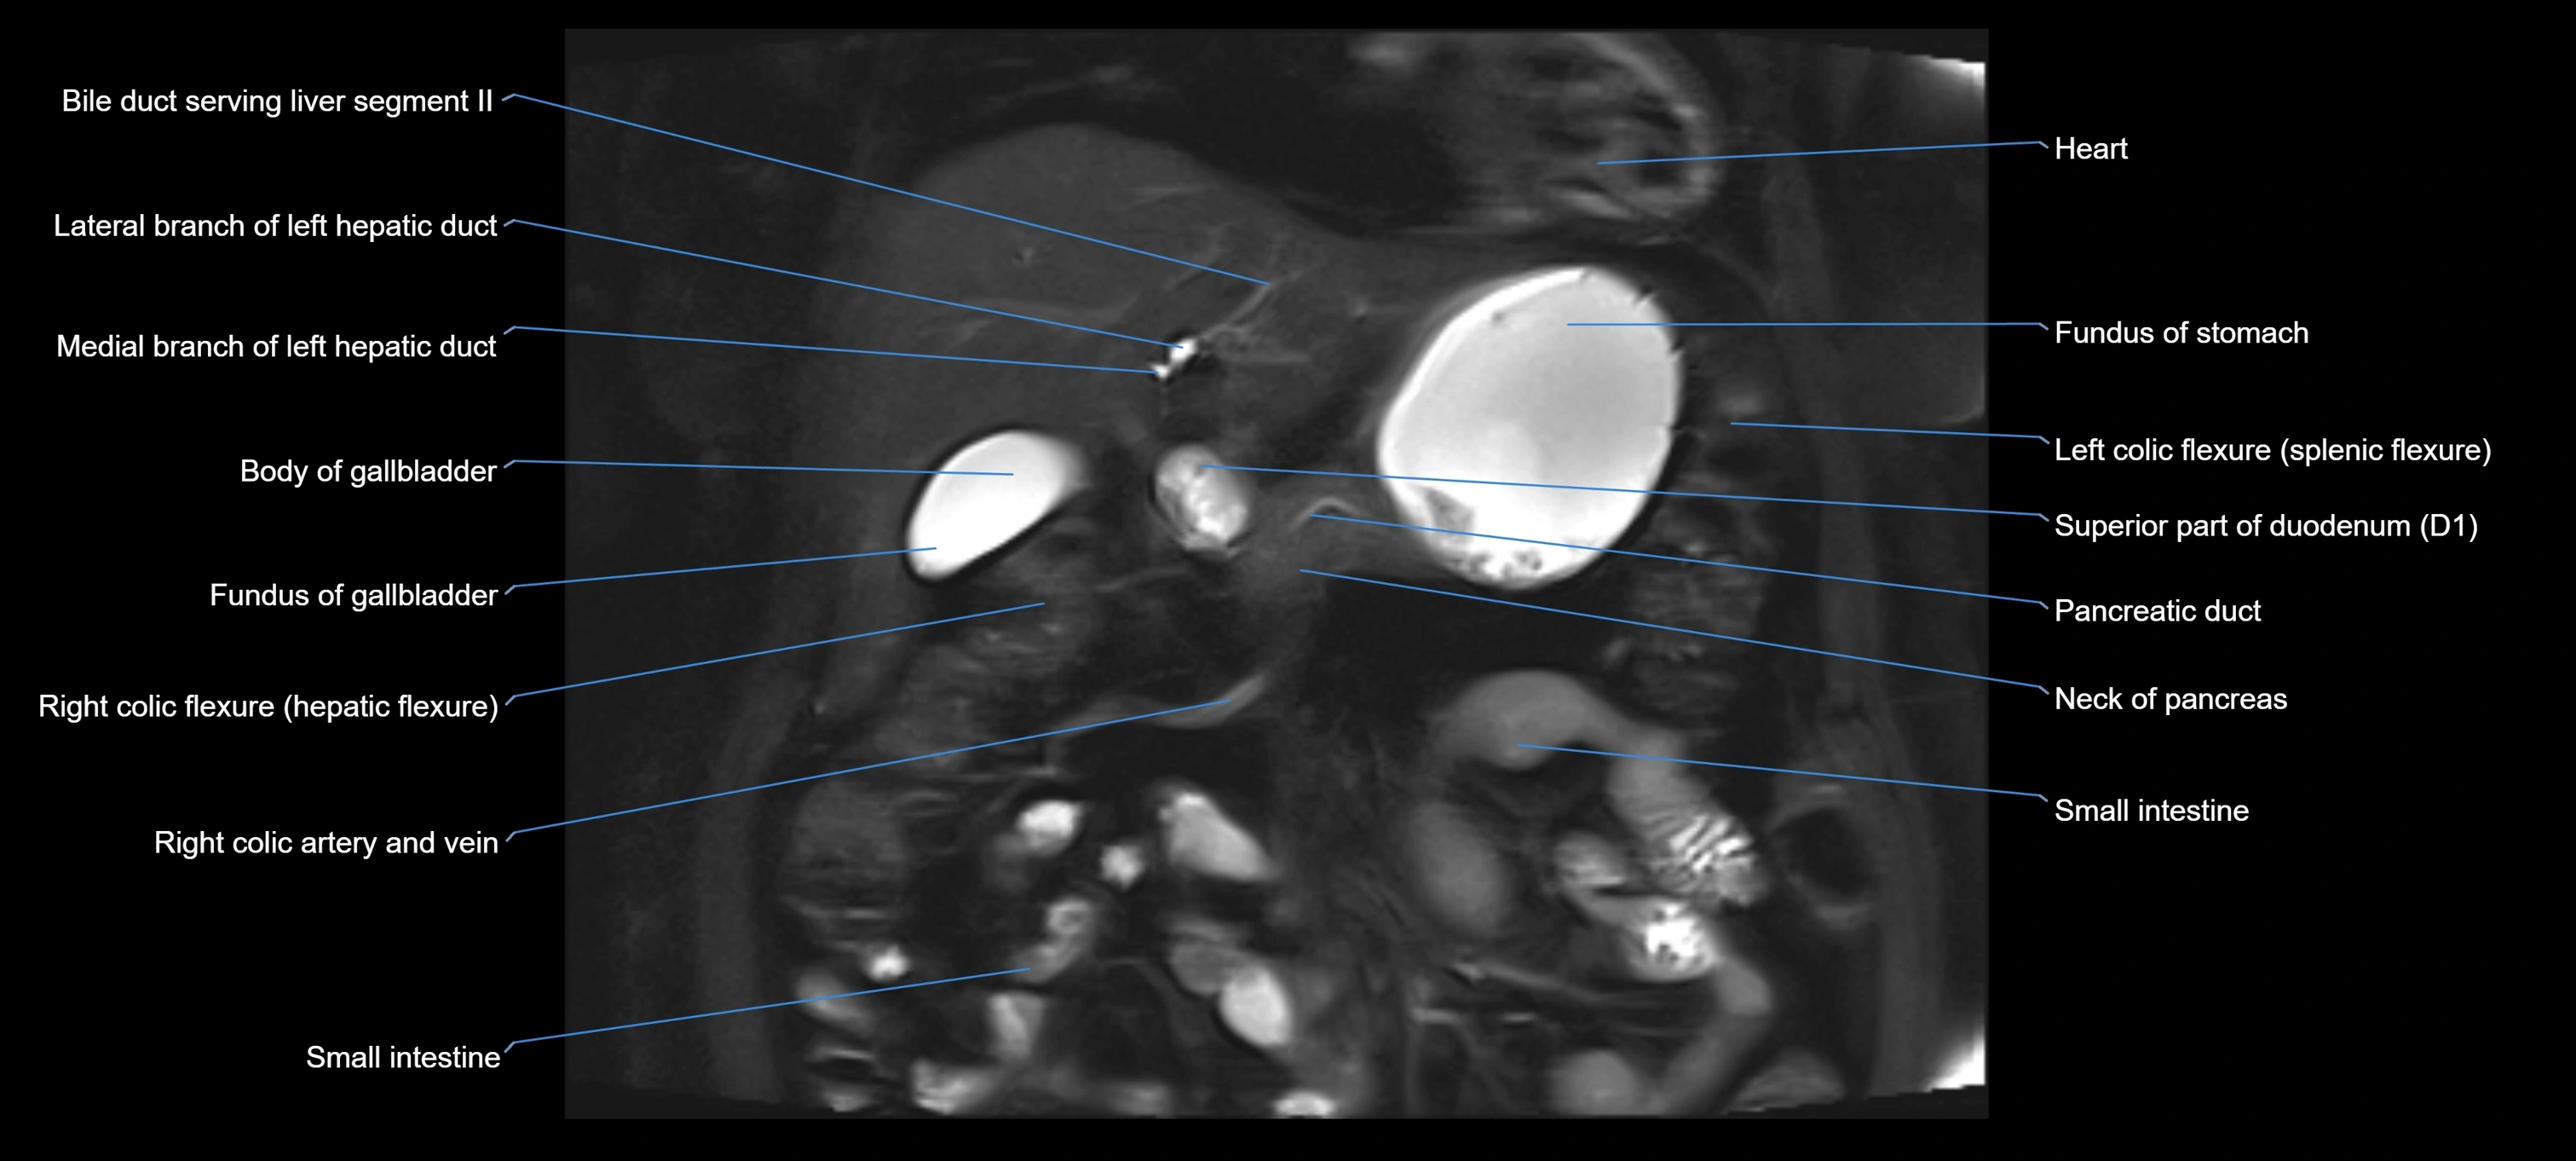

MRI image

image